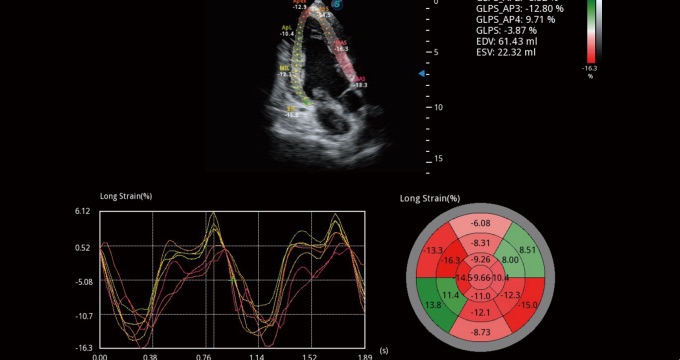

• Análisis Cuantitativo del Miocardio (MQA)

La medición cuantitativa precisa de la mecánica del miocardio se logra mediante un MQA basado en el monitoreo sensible del movimiento de la pared en tiempo real. Proporciona una evaluación global y regional que incluye deformación, tasa de deformación, desplazamiento, velocidad, etc.

A4C con TDI